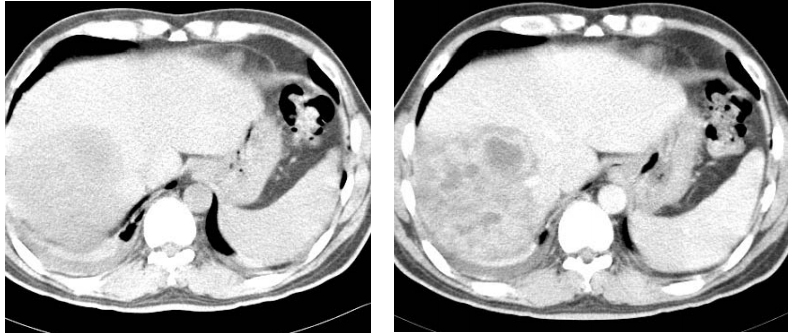

74 73 歲林先生,因發燒、畏寒、右上腹部疼痛而被家人送醫。醫師為他叩診(percussion)發現肋間肝 臟處有敲擊痛。注射對比劑前、後 CT 顯示肝右葉病變如圖示。林先生最可能患了什麼病? (A)肝臟海綿狀血管瘤(cavernous hemangioma) (B)肝膿瘍(liver abscess) (C)局部性脂肪肝(focal fatty infiltration) (D)轉移病變(liver metastasis)